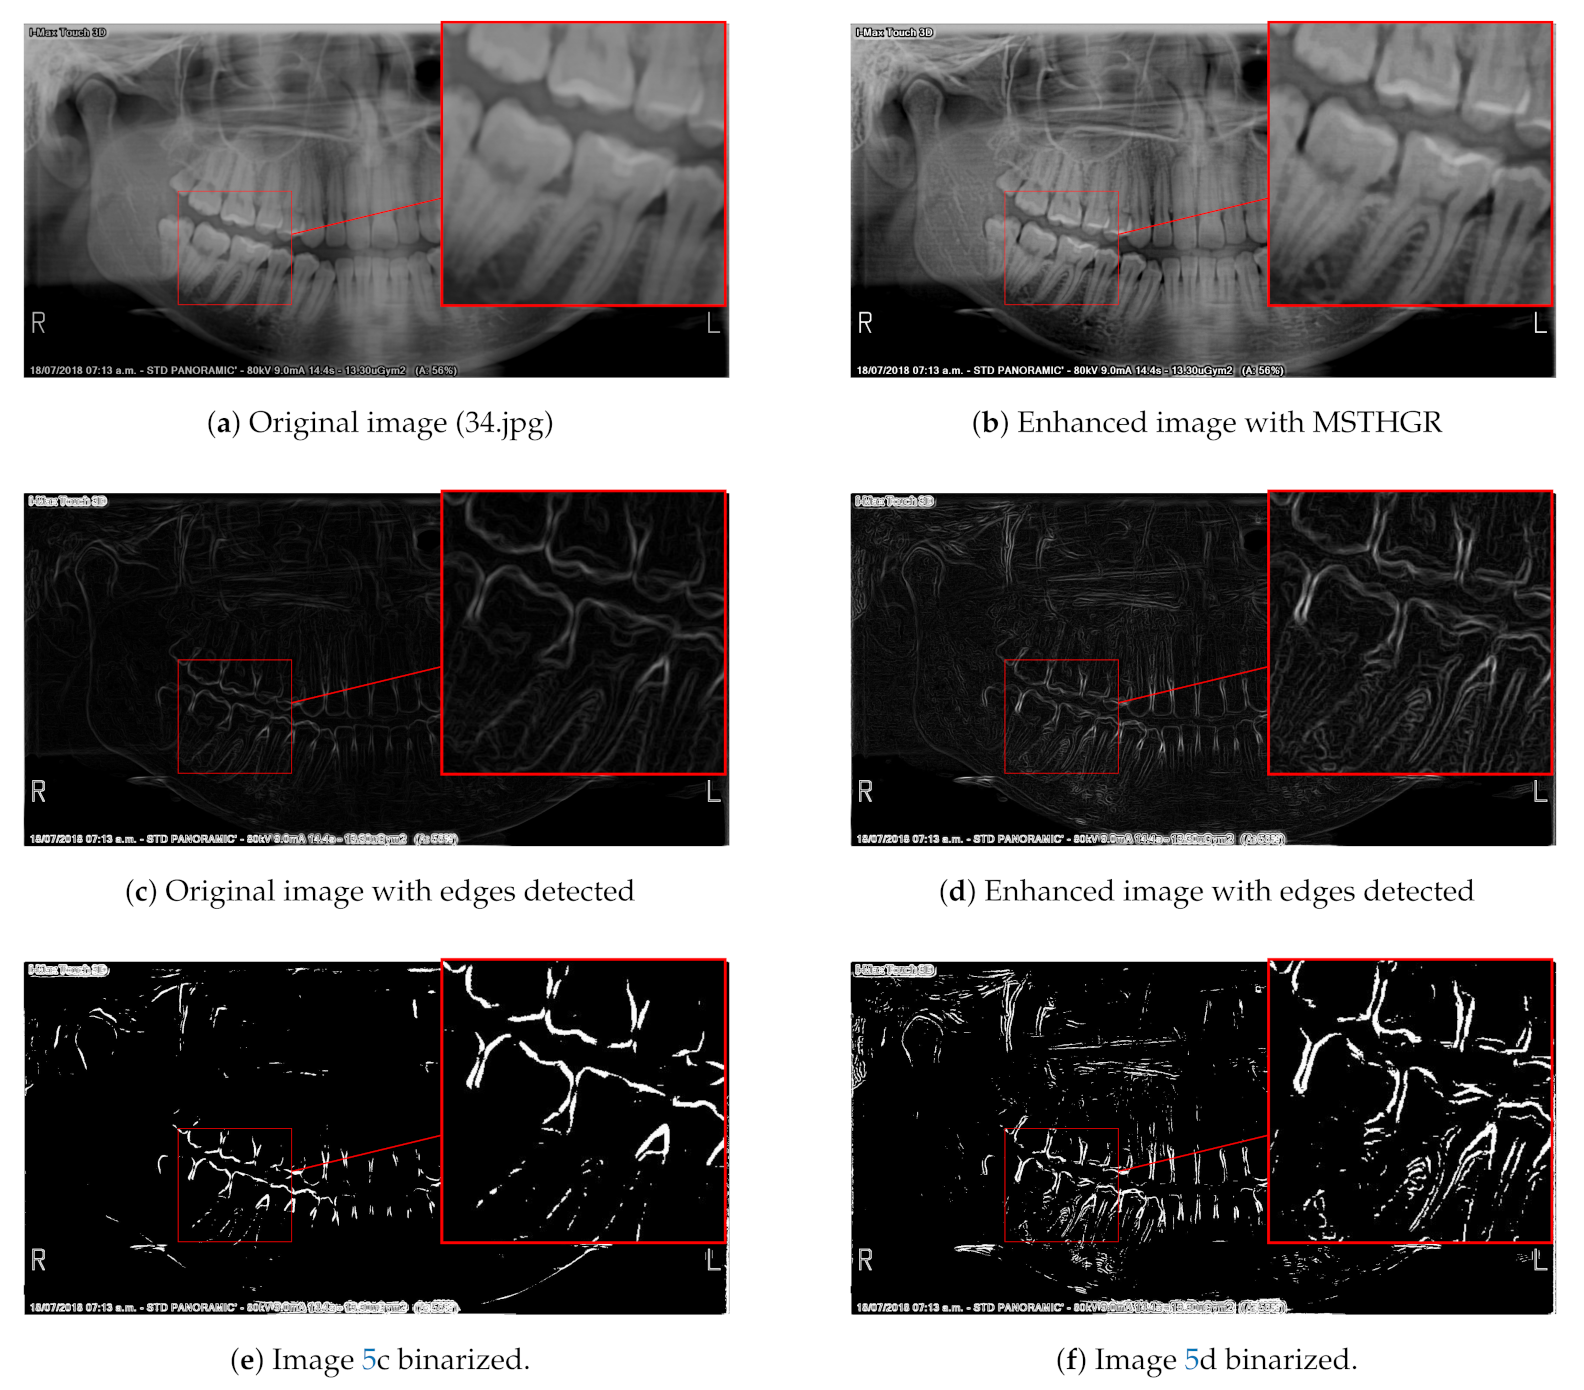

3.3. Numerical and Visual Results

- For the REC metric, MSTHGR was numerically superior to the GRMMCE, QHELC and GC algorithms.

- For the CIR metric, MSTHGR was numerically superior to the GRMMCE, HE, BBHE, DSIHE, MMBEBHE, QHELC and CLAHE algorithms.

- For the E metric, MSTHGR was numerically superior to the GRMMCE, HE, BBHE, DSIHE, MMBEBHE, QHELC and GC algorithms.

- For the SF metric, MSTHGR was numerically superior to all compared algorithms.

- For the PSNR metric, MSTHGR was numerically superior to the HE, BBHE, DSIHE, MMBEBHE and CLAHE algorithms.

- For the AMBE metric, MSTHGR was numerically superior to the HE, BBHE, DSIHE, MMBEBHE, CLAHE and GC algorithms.